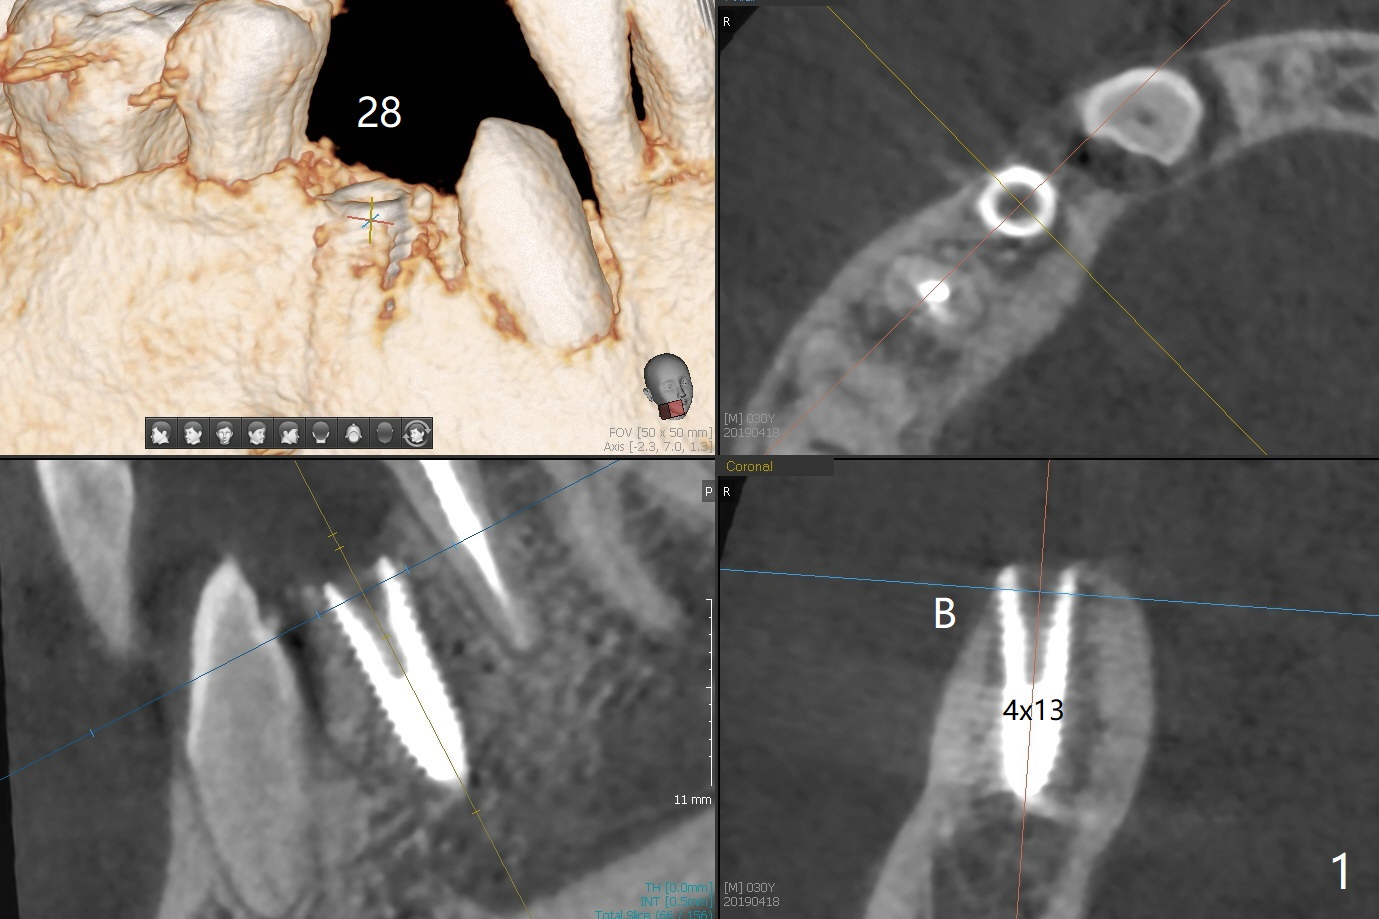

When the surgical guide for #28 is removed, the 4x13 mm implant is found to be superficial and buccal. Part of the buccal mucosa is nonkeratinized. After 1 mm deeper placement of the implant, CT confirms the buccal placement (Fig.1, as compared to design). In fact the guide was doubly checked for fitness prior to osteotomy, but grossly it seemed to be seated properly. The suspicion is related to the trimming at the site of #27 (Fig.2,3 (*), as compared to a mounted model in Fig.4,5 (arrowhead) and the model sent to lab for guide fabrication). The lab agrees to redesign the case. There is a narrow buccal band 1 week postop (Fig.6). The patient is a smoker. The implant was placed buccal (Fig.7, 1 month postop). A new 4x13 mm implant is placed on the top of the 1st line following 3x14.5 mm drill (Fig.8 (35 Ncm)). In fact the implant position is not changed much. Four months post banding (20 ss) and 2 months post 2nd implant placement, the tooth #27 is exposed for bracket; extrusion is initiated (Fig.9). In 3 weeks of retraction, the bracket is supragingival (Fig.10). The canine contacts the distal healing abutment with 2 months of retraction (Fig.11). It seems necessary to initiate lower bracket placement. There is no bone loss 4 months postop (Fig.12). A 4.5x7(4) mm abutment is placed (Fig.13) for a temporary crown as an anchor (Fig.14) to further extrude #27 with continuous inter-arch retraction (to reduce tension upon #26 with severe bone loss (Fig.12)). LR3 extrusion is incomplete, although there is an increase in bone distal to LR2 ~ 10 months of extrusion (Fig.15).